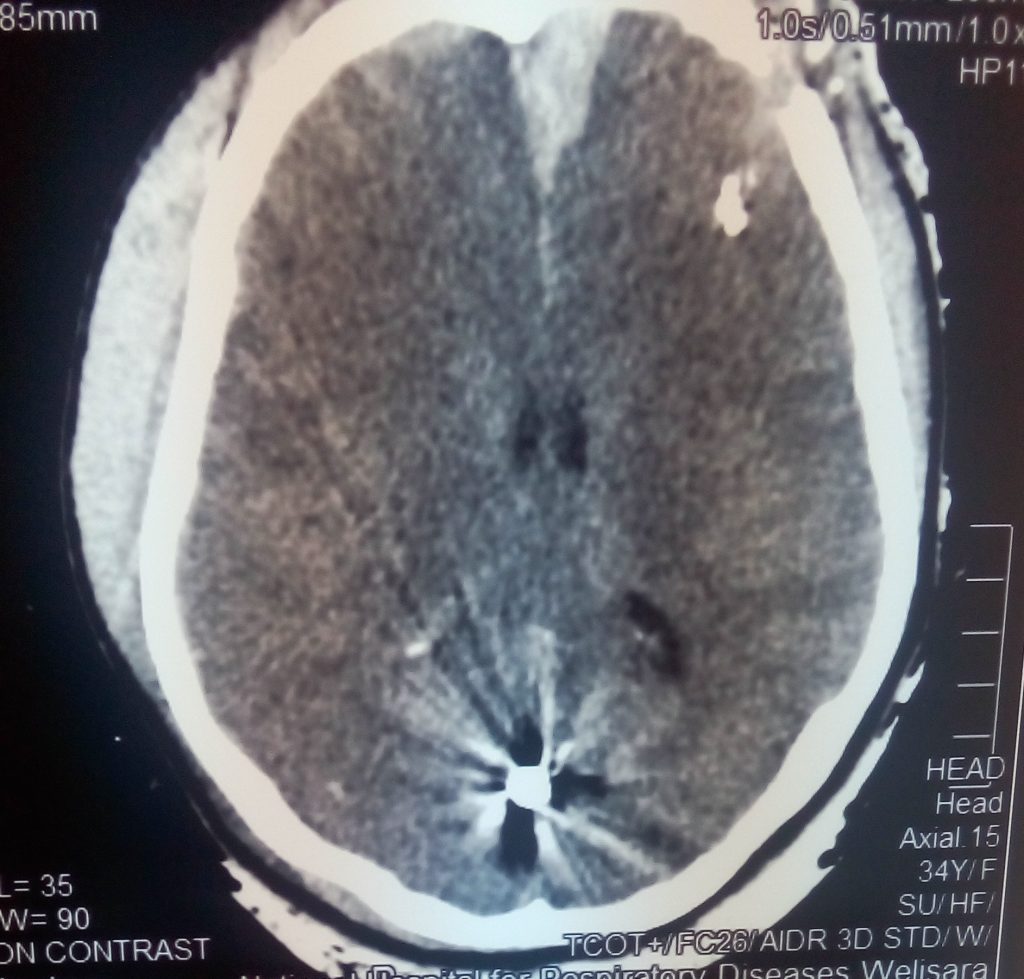

3.Tertiary-Results from individuals being thrown by the blast wind. Any body part may be affected. Types of Injuries-Fracture and traumatic amputation, Closed and open brain injury